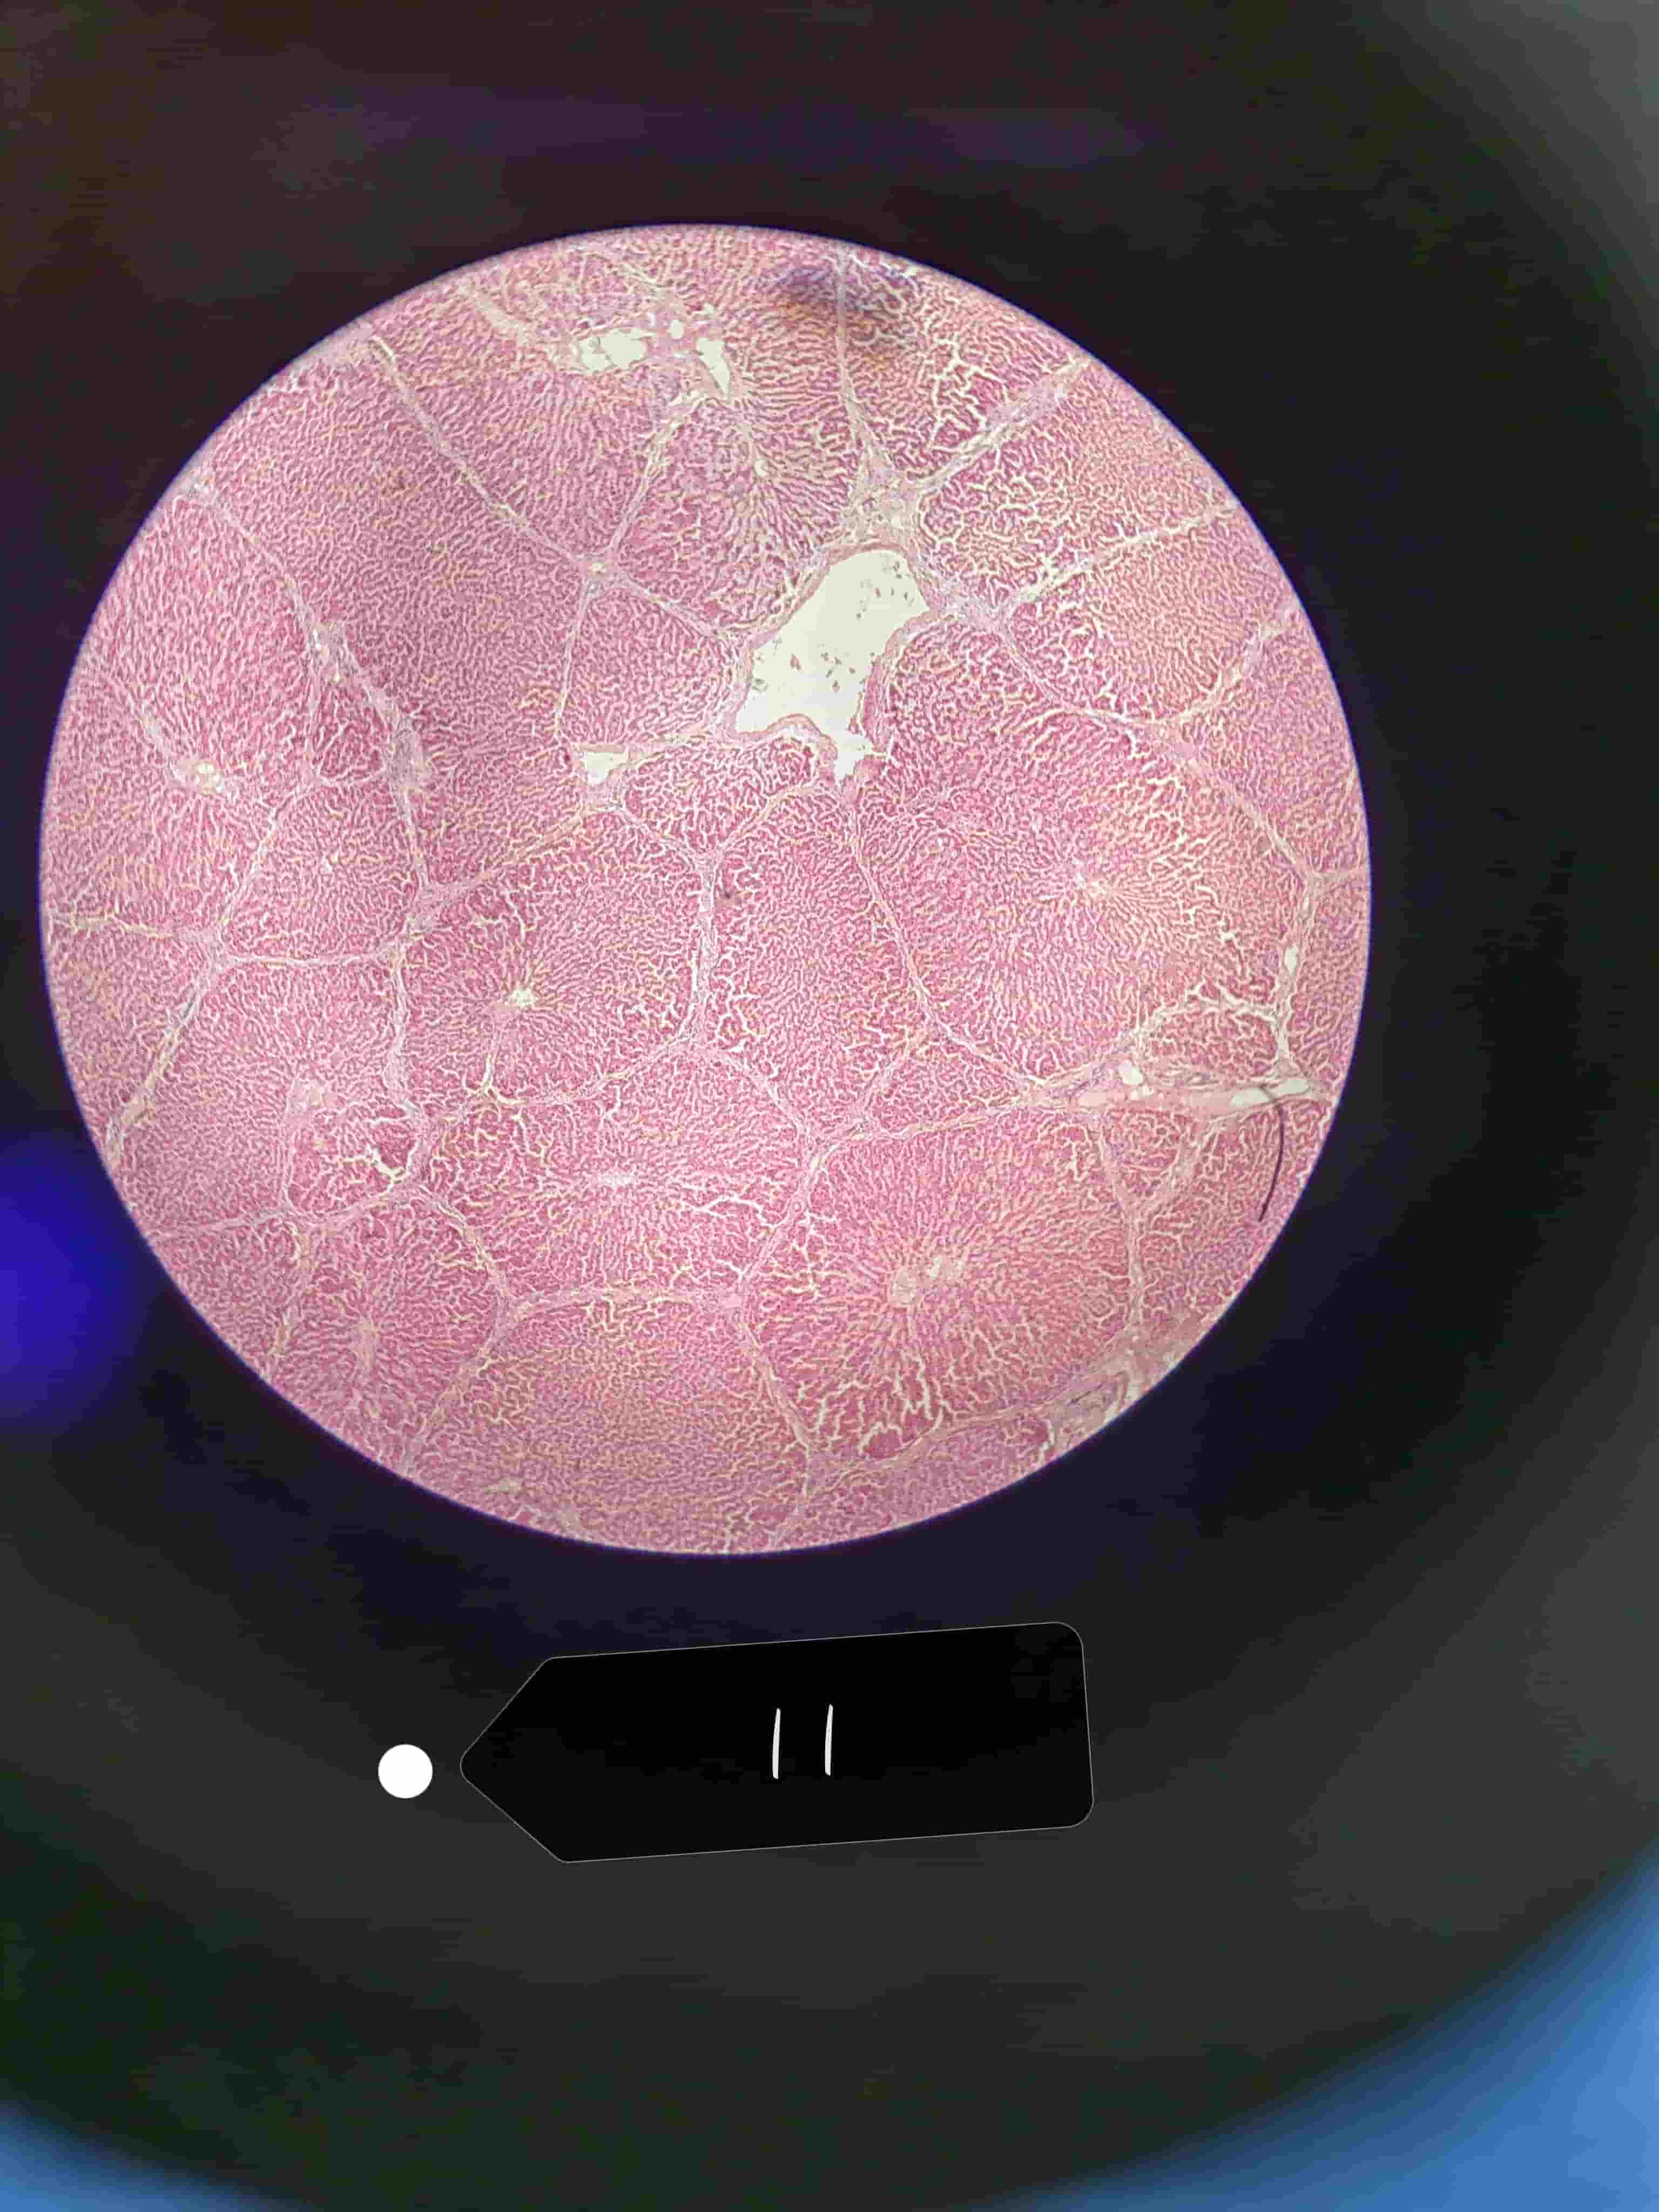

肝脏

肝小叶,几个小叶之间有门管区

肝血窦